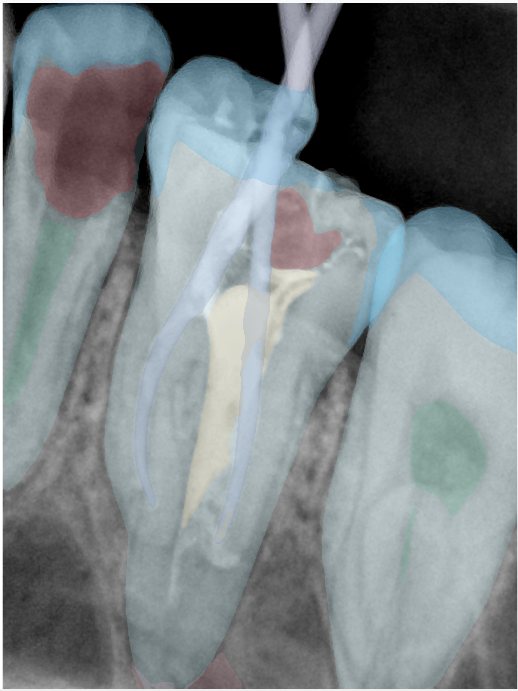

CR/DR 牙齿分割阶段记录

当前进展

- 完成了 CR/DR 牙齿相关分割训练

- 当前结果已经达到阶段预期,但仍有细节问题需要继续处理

相关测试

遇到的问题

- 训练过程中出现过 mask 下移问题

- 部分结果会出现 box 填充异常

- mask 边缘仍然有比较明显的锯齿感

参考

第二版算法问题测试